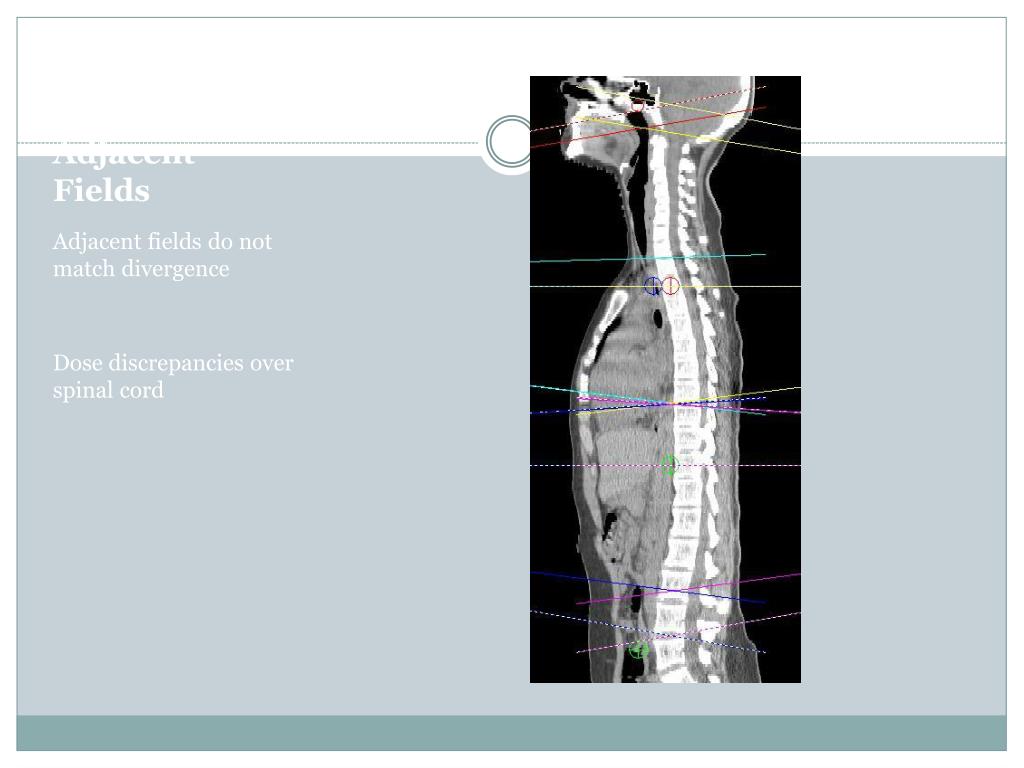

18. Adjacent Fields Adjacent fields do not match divergence Dose discrepancies over spinal cord